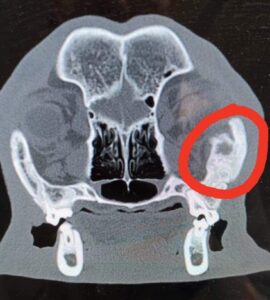

Dalsza diagnostyka problemu z otwieraniem pyszczka obejmowała najpierw zdjęcia RTG, a potem Tomograf, który w tym przypadku był niezbędnym badaniem diagnostycznym. Tomograf ujawnił rozrost tkanki kostnej pomiędzy szczęką (łukiem jarzmowym) a żuchwą (wyrostkiem dziobiastym gałęzi żuchwy), co powodowało, że pyszczek praktycznie się nie otwierał.